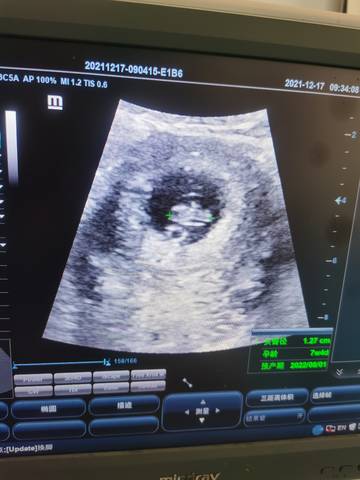

有人会根据孕囊看男孩女孩吗?

journal_insert_pic_1681544530

你好根据这个是看不出男女的只要宝宝健康才是我们最大的心愿不是吗?最后祝宝妈心想事成哦。

通过这些是看不出来的,而且也不准确,在怀孕期间,我觉得只要宝宝发育好的话,还是不要想太多了,男孩女孩都一样的。

你好,对于宝宝是男孩女孩,怀孕的单子、数据、表现是判断不出来的,只有生下来才是最靠谱的,在这也愿你心想事成。